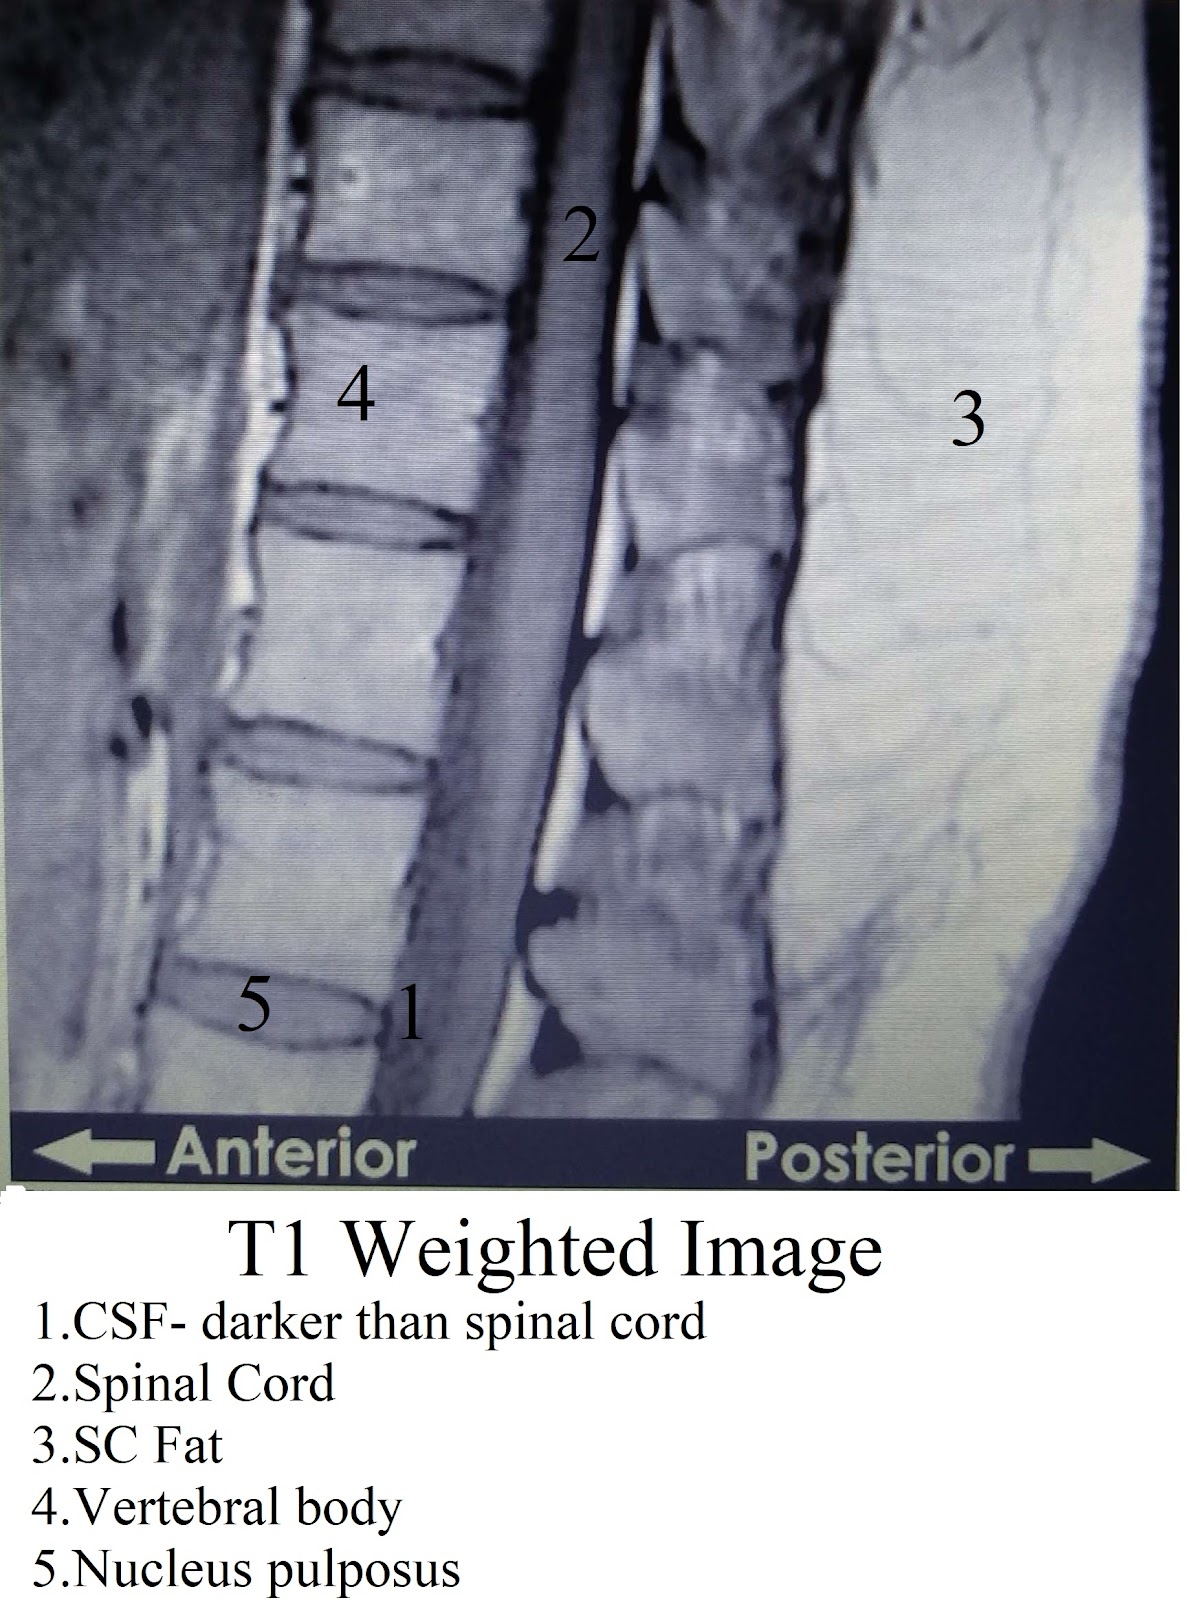

From the medical point of view the T1 and T2 weighted images are used to highlight different constituents of various tissues.

T1 weighted images highlight only fat containing tissues in the body.

Note that the fat appears bright on both T1 and T2 images.

A: Compare it with the T1 image. Fat would appear white on both the images (subcutaneous fat in the above images) whereas water based tissue would appear dark on T1 and get highlighted on T2 images( CSF in the above photos).

The T1 weighted image is useful to delineate the normal anatomy whereas certain pathologies become easily appreciable with the T2 images.

During the process of T1 relaxation, protons reorient back to their longitudinal position in the magnetic field created. Fat quickly realigns its longitudinal magnetization and therefore appears bright on a T1 weighted image.

Conversely, water has much slower longitudinal magnetization realignment after an RF pulse and therefore, water has low signal and appears dark.